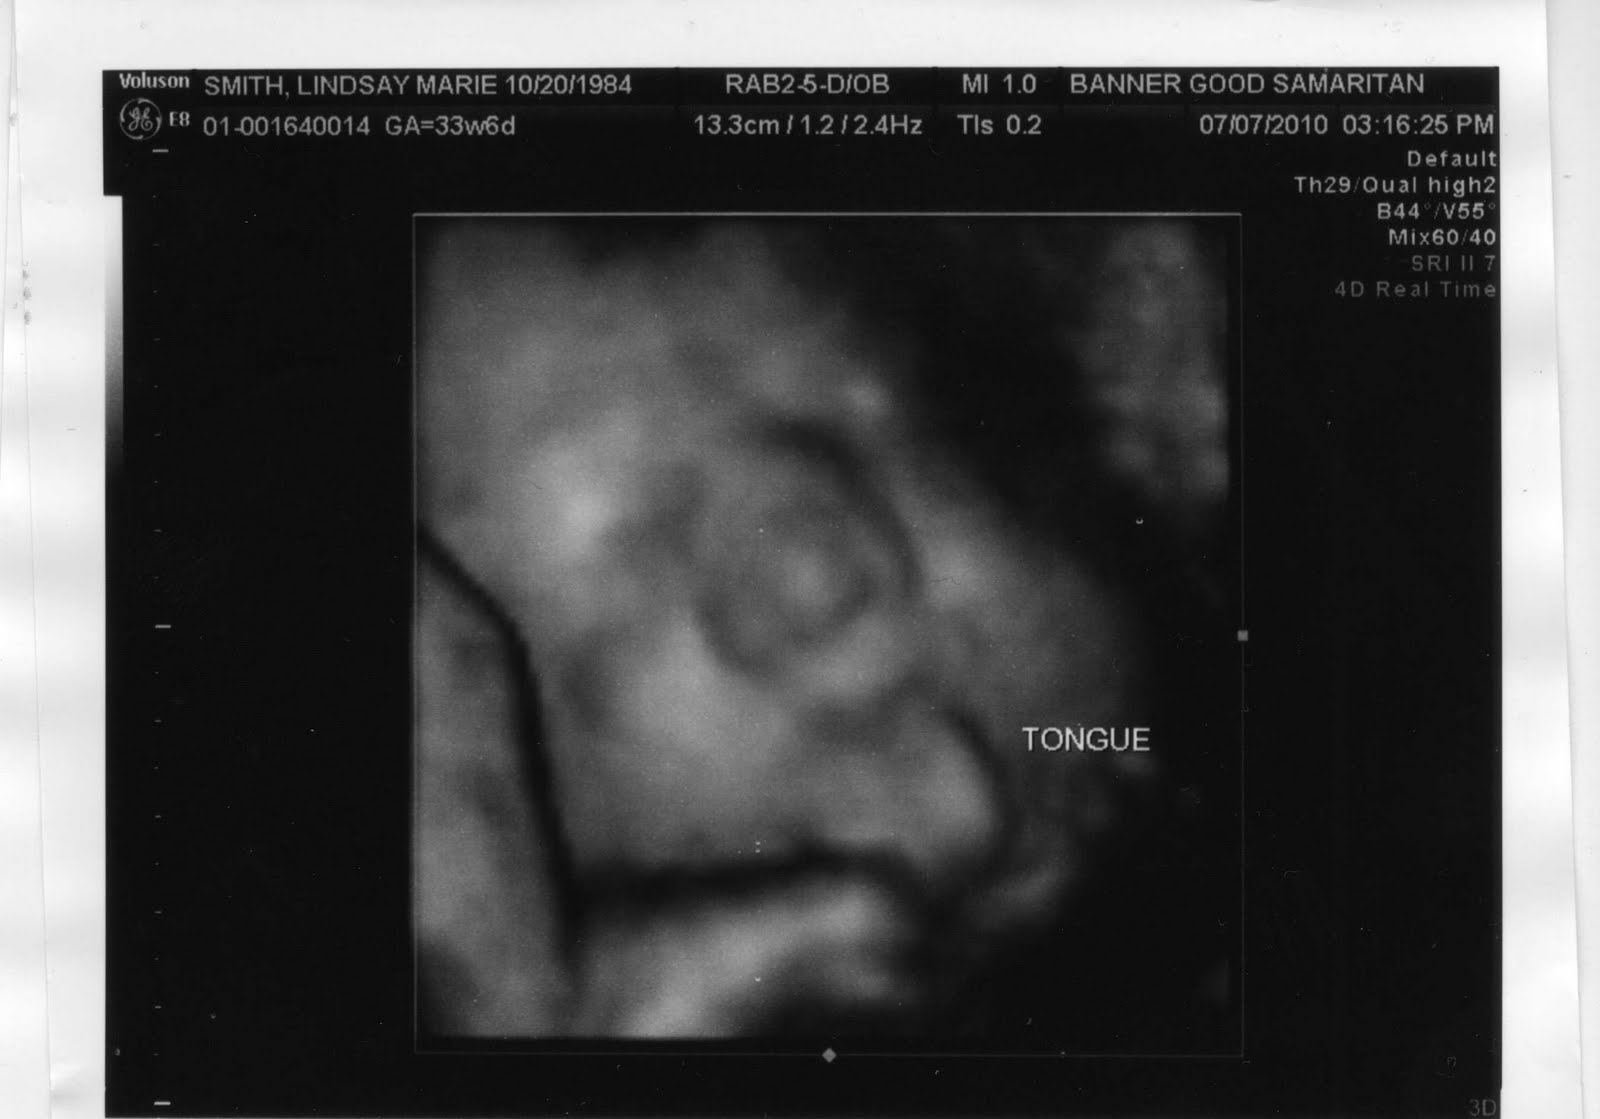

Lindsay had another appointment today where she got another ultrasound. This time we got the super cool 3D pictures... and here they are.

This picture is awesome, My little bratty princess, Ha!

So those are the very first images where we get to see my beautiful daughter. Pretty soon we'll get to see the real thing... just a few weeks away...